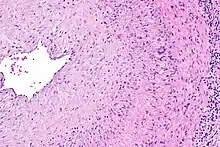

Histological features of temporal arteritis

Intermediate magnification micrograph showing giant cell arteritis in a temporal artery biopsy. The arterial lumen is seen on the left. A giant cell is seen on the right at the interface between the thickened intima and media. H&E stain